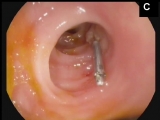

A 58-year-old man was admitted to the hospital with hematochezia and anemia (Hb of 9 mg/dL, normal levels: 12-15 mg/dL) without hemodynamic instability. Gastroscopy showed erosive antritis and colonoscopy with ileoscopy was normal. The patient was discharged on pantoprazole and iron supplementation. Two weeks latter the patient was admitted with a new episode of hematochezia with hemodynamic instability and a Hb of 6.3 mg/dL. He was transfused three packed blood cells units. Gastroscopy was normal. Colonoscopy yielded blood in the ascending colon and cecum without any mucosal abnormalities. Small amounts of blood were also seen in the terminal ileum without an evident source of bleeding. After profuse washing a 1-mm mucosal defect with a central slightly protruding vessel consistent with a Dieulafoy’s lesion was seen. The lesion spontaneously began to bleed in a pulsating fashion (A). Treatment with argon plasma coagulation (30W) and thermocoagulation using bipolar probe failed to stop the bleeding (B). Finally, a hemoclip was placed resulting in immediate hemostasis. The patient was discharged 4 days after the procedure (C, Video). There were no further episodes of bleeding 6 months afterwards.

Figura C